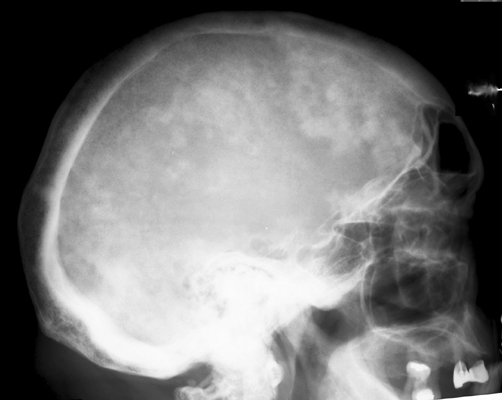

Diagnosis:Paget's Disease Discussion:Plain film of the skull reveals a large mottled area of radiolucency with small areas of increased density within it. The MR image of the skull reveals a thickened, enlarged cranium with increase in the marrow space. Two bone scan images also reveal increased activity in the skull, more localized to one side, characteristic to the localized disease seen in Paget's. This is classic cranial involvement of Paget's. In the cranium, bone sclerosis may produce circular radiodense lesions in one area, whereas osteoporosis circumscripta is noted elsewhere. In the skull, the common region of involvement is the cranial vault. The osteolytic phase is called osteoporosis circumscripta and appears as multiple geographic, well-demarcated regions of bone resorption that may be mistaken for metastases. Focal radiodensities occur as pagetoid bone is formed. In the quiescent phase, there is a radiodense cotton-wool appearance with a thickened vault. References: